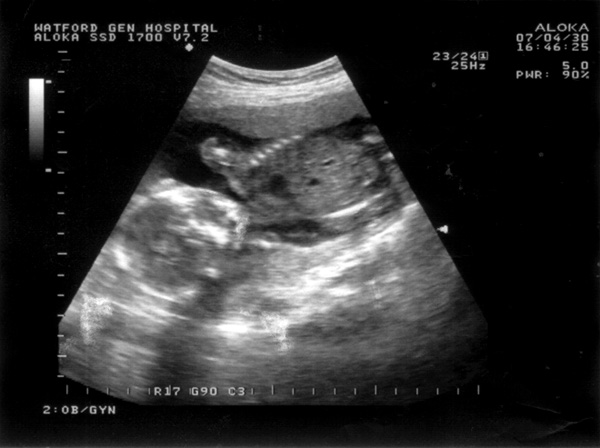

First scan, 30th April 2007, (19 weeks)